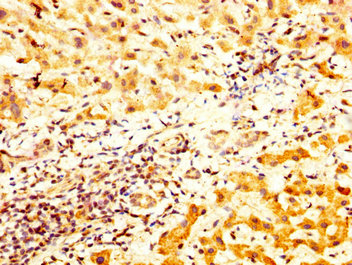

IHC image of CSB-PA023320LA01HU diluted at 1:800 and staining in paraffin-embedded human liver cancer performed on a Leica BondTM system. After dewaxing and hydration, antigen retrieval was mediated by high pressure in a citrate buffer (pH 6.0). Section was blocked with 10% normal goat serum 30min at RT. Then primary antibody (1% BSA) was incubated at 4°C overnight. The primary is detected by a biotinylated secondary antibody and visualized using an HRP conjugated SP system.